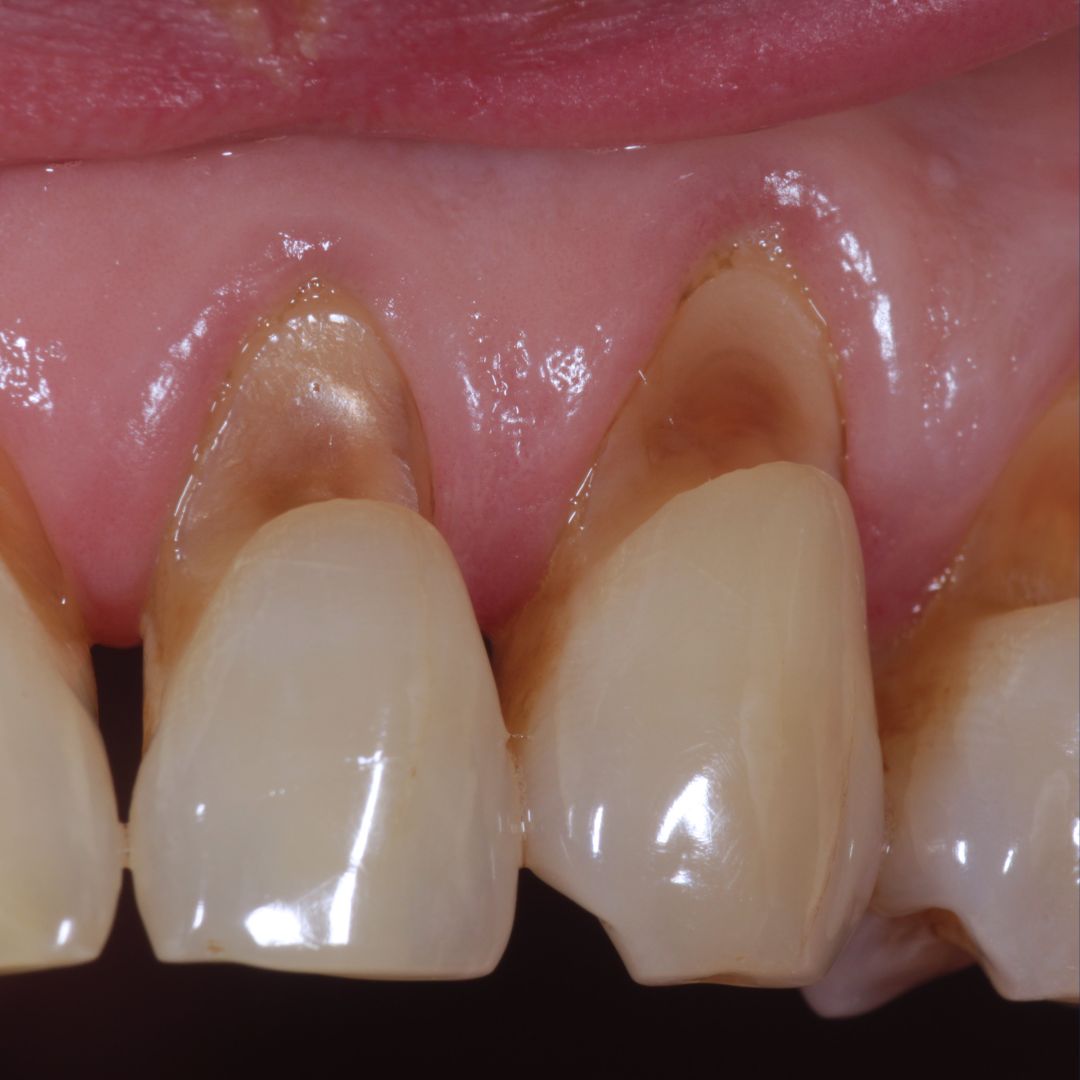

Symptoms and Signs: What Does Tooth Abrasion Look Like?

Tooth abrasion typically appears as:

- V-shaped notches or wedges at the gumline

- Yellowing of the affected area (as dentin becomes exposed)

- Increased sensitivity to hot, cold, sweet, or acidic foods

- Rough or uneven tooth surface

Tooth Abrasion at the Gumline: A Common Problem

The area where your tooth meets the gum is particularly vulnerable to abrasion. This junction, called the cervical area, has thinner enamel and is often where we see those characteristic V-shaped notches.

Why Is This Area So Vulnerable?

- The enamel is naturally thinner here

- Gum recession can expose the root surface, which is covered by cementum (softer than enamel)

- It’s often missed during brushing, leading to compensatory aggressive brushing later